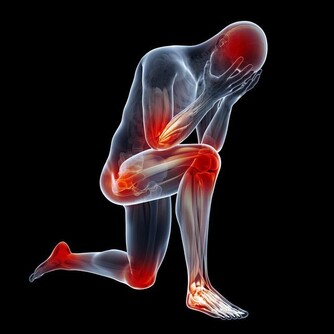

1.如果感覺到了肩周炎的典型症狀:肩膀疼痛、關節活動受限,

但同時還有低熱、盜汗、乏力、臉色蒼白、消瘦等症狀,要提防肩關節結核。

2.肩部腫瘤也會引起肩痛、肩臂活動功能障礙,

如果覺得肩痛逐漸加重、疼痛部位擴大,可別再「惦記」肩周炎,一定要做進一步檢查。

3.多數膽囊炎的首發症狀是背疼,或是右肩、右肩胛下隱痛。

要還有噁心、腹脹、反酸、胃部灼燒感等消化不良症狀,別忘了去醫院做個彩超檢查一下膽囊。

4.患有高血壓的中老年人,突然覺得背疼,或是前胸、腹部疼痛難忍,

像是身體被刀割或是撕裂了似的,有可能是主動脈夾層,一定要儘快就醫。

如果搶救不及時,約四成患者可能會在24小時內死亡。

5.心絞痛、心肌梗死,也會放射至後背、左肩等部位,冠心病患者要是突然覺得肩背疼要小心。